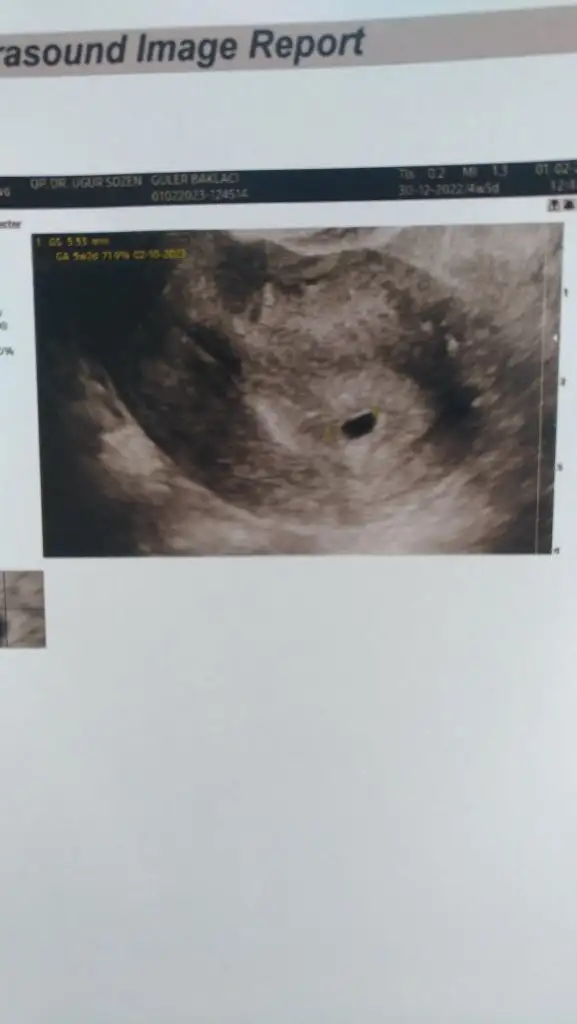

Kızlar hepinizi ayrı ayrı tebrik ederimKızlar bugün kontrole gittim duruyormu diştümü diye geçen hafta kesem boştu bugün 6+3 te kesem biraz düzelmişt ve bebekte göründü ucundanoynayan birşeyler vardı ama kalp sesi duyulmadı bir hagta daha bekleyeceğiz kalp atışı icin. Atarsa yola devam atmazsa bebeğim adaya veda edecek dualarınızda bana da yer vermeyi unutmayın:)